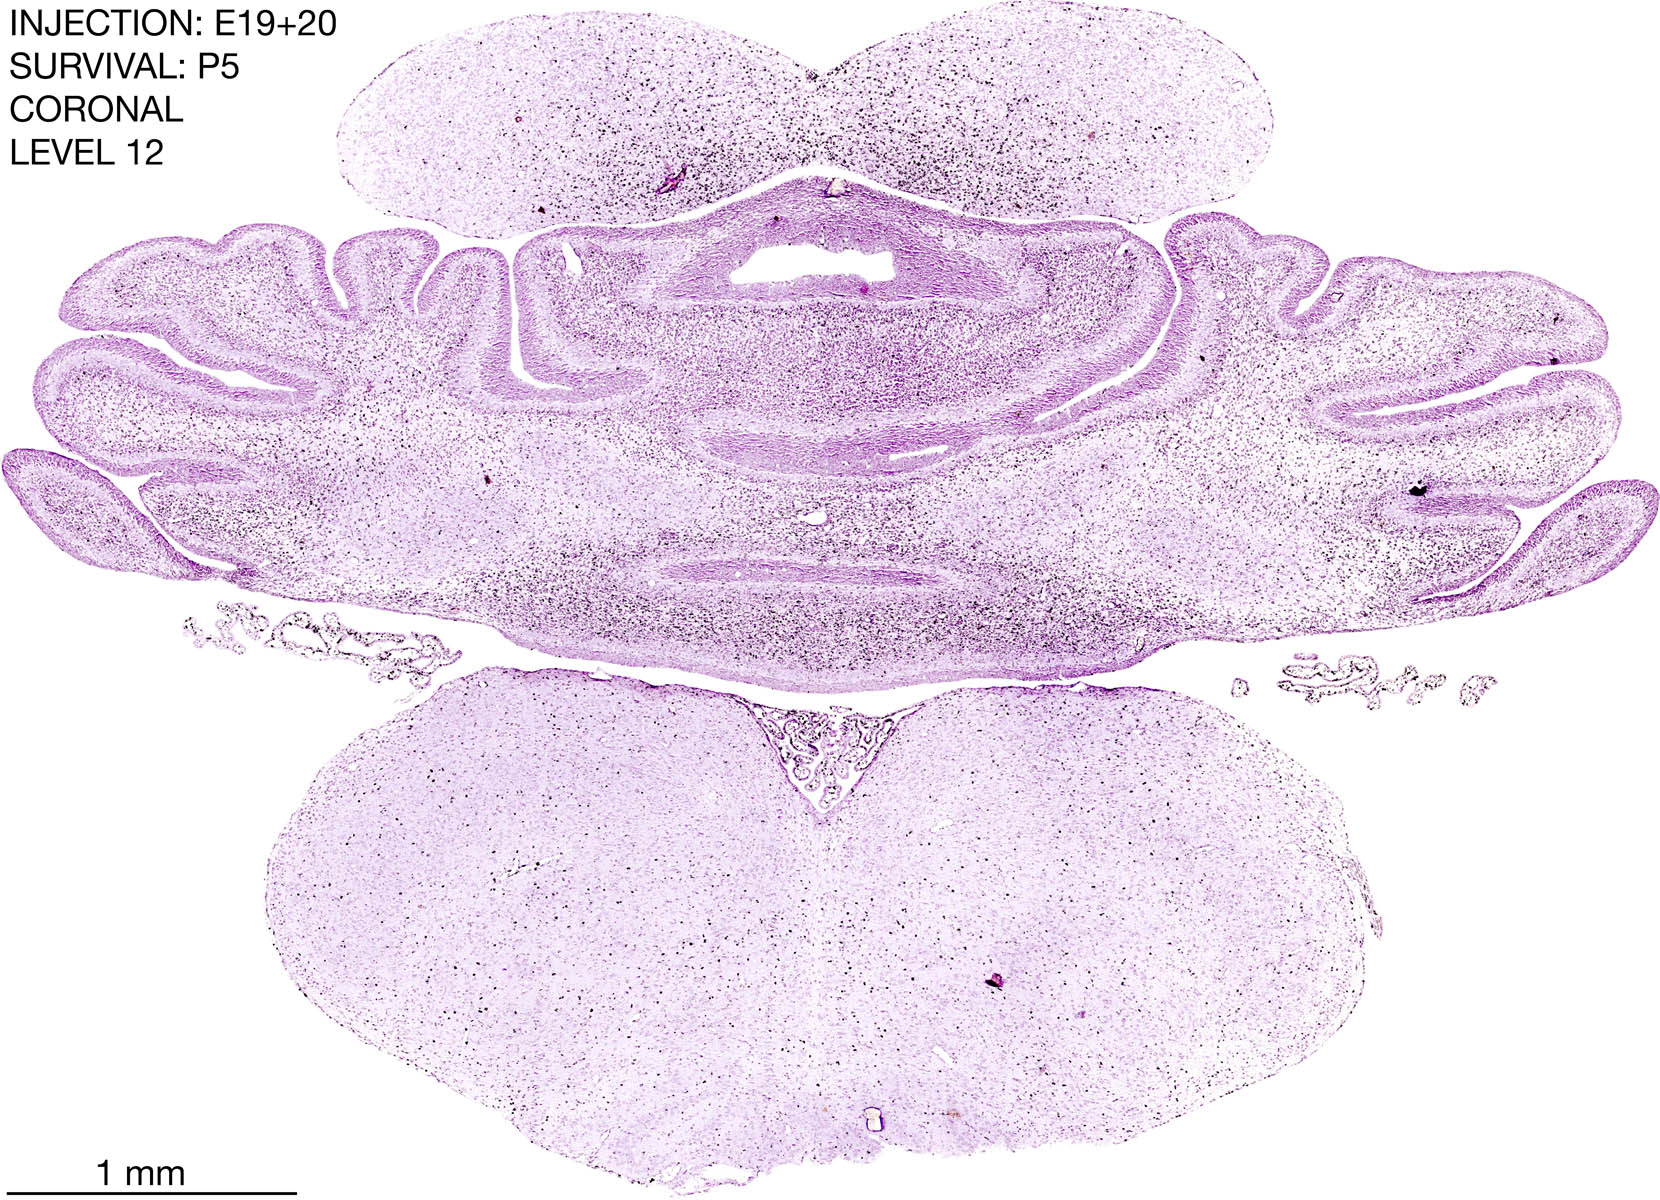

E19+20 P5 Survival The images below are from the brain of a rat that was exposed to tritiated thymidine on E19+20 and survived to P5. Download: Large | High Res Download: Large | High Res Download: Large | High Res Download: Large | High Res Download: Large | High Res Download: Large | High Res Download: Large | High Res Download: Large | High Res Download: Large | High Res Download: Large | High Res Download: Large | High Res Download: Large | High Res Download: Large | High Res Download: Large | High Res Download: Large | High Res Download: Large | High Res Download: Large | High Res Download: Large | High Res Download: Large | High Res Download: Large | High Res Download: Large | High Res Download: Large | High Res Download: Large | High Res Download: Large | High Res Download: Large | High Res Download: Large | High Res Download: Large | High Res Download: Large | High Res